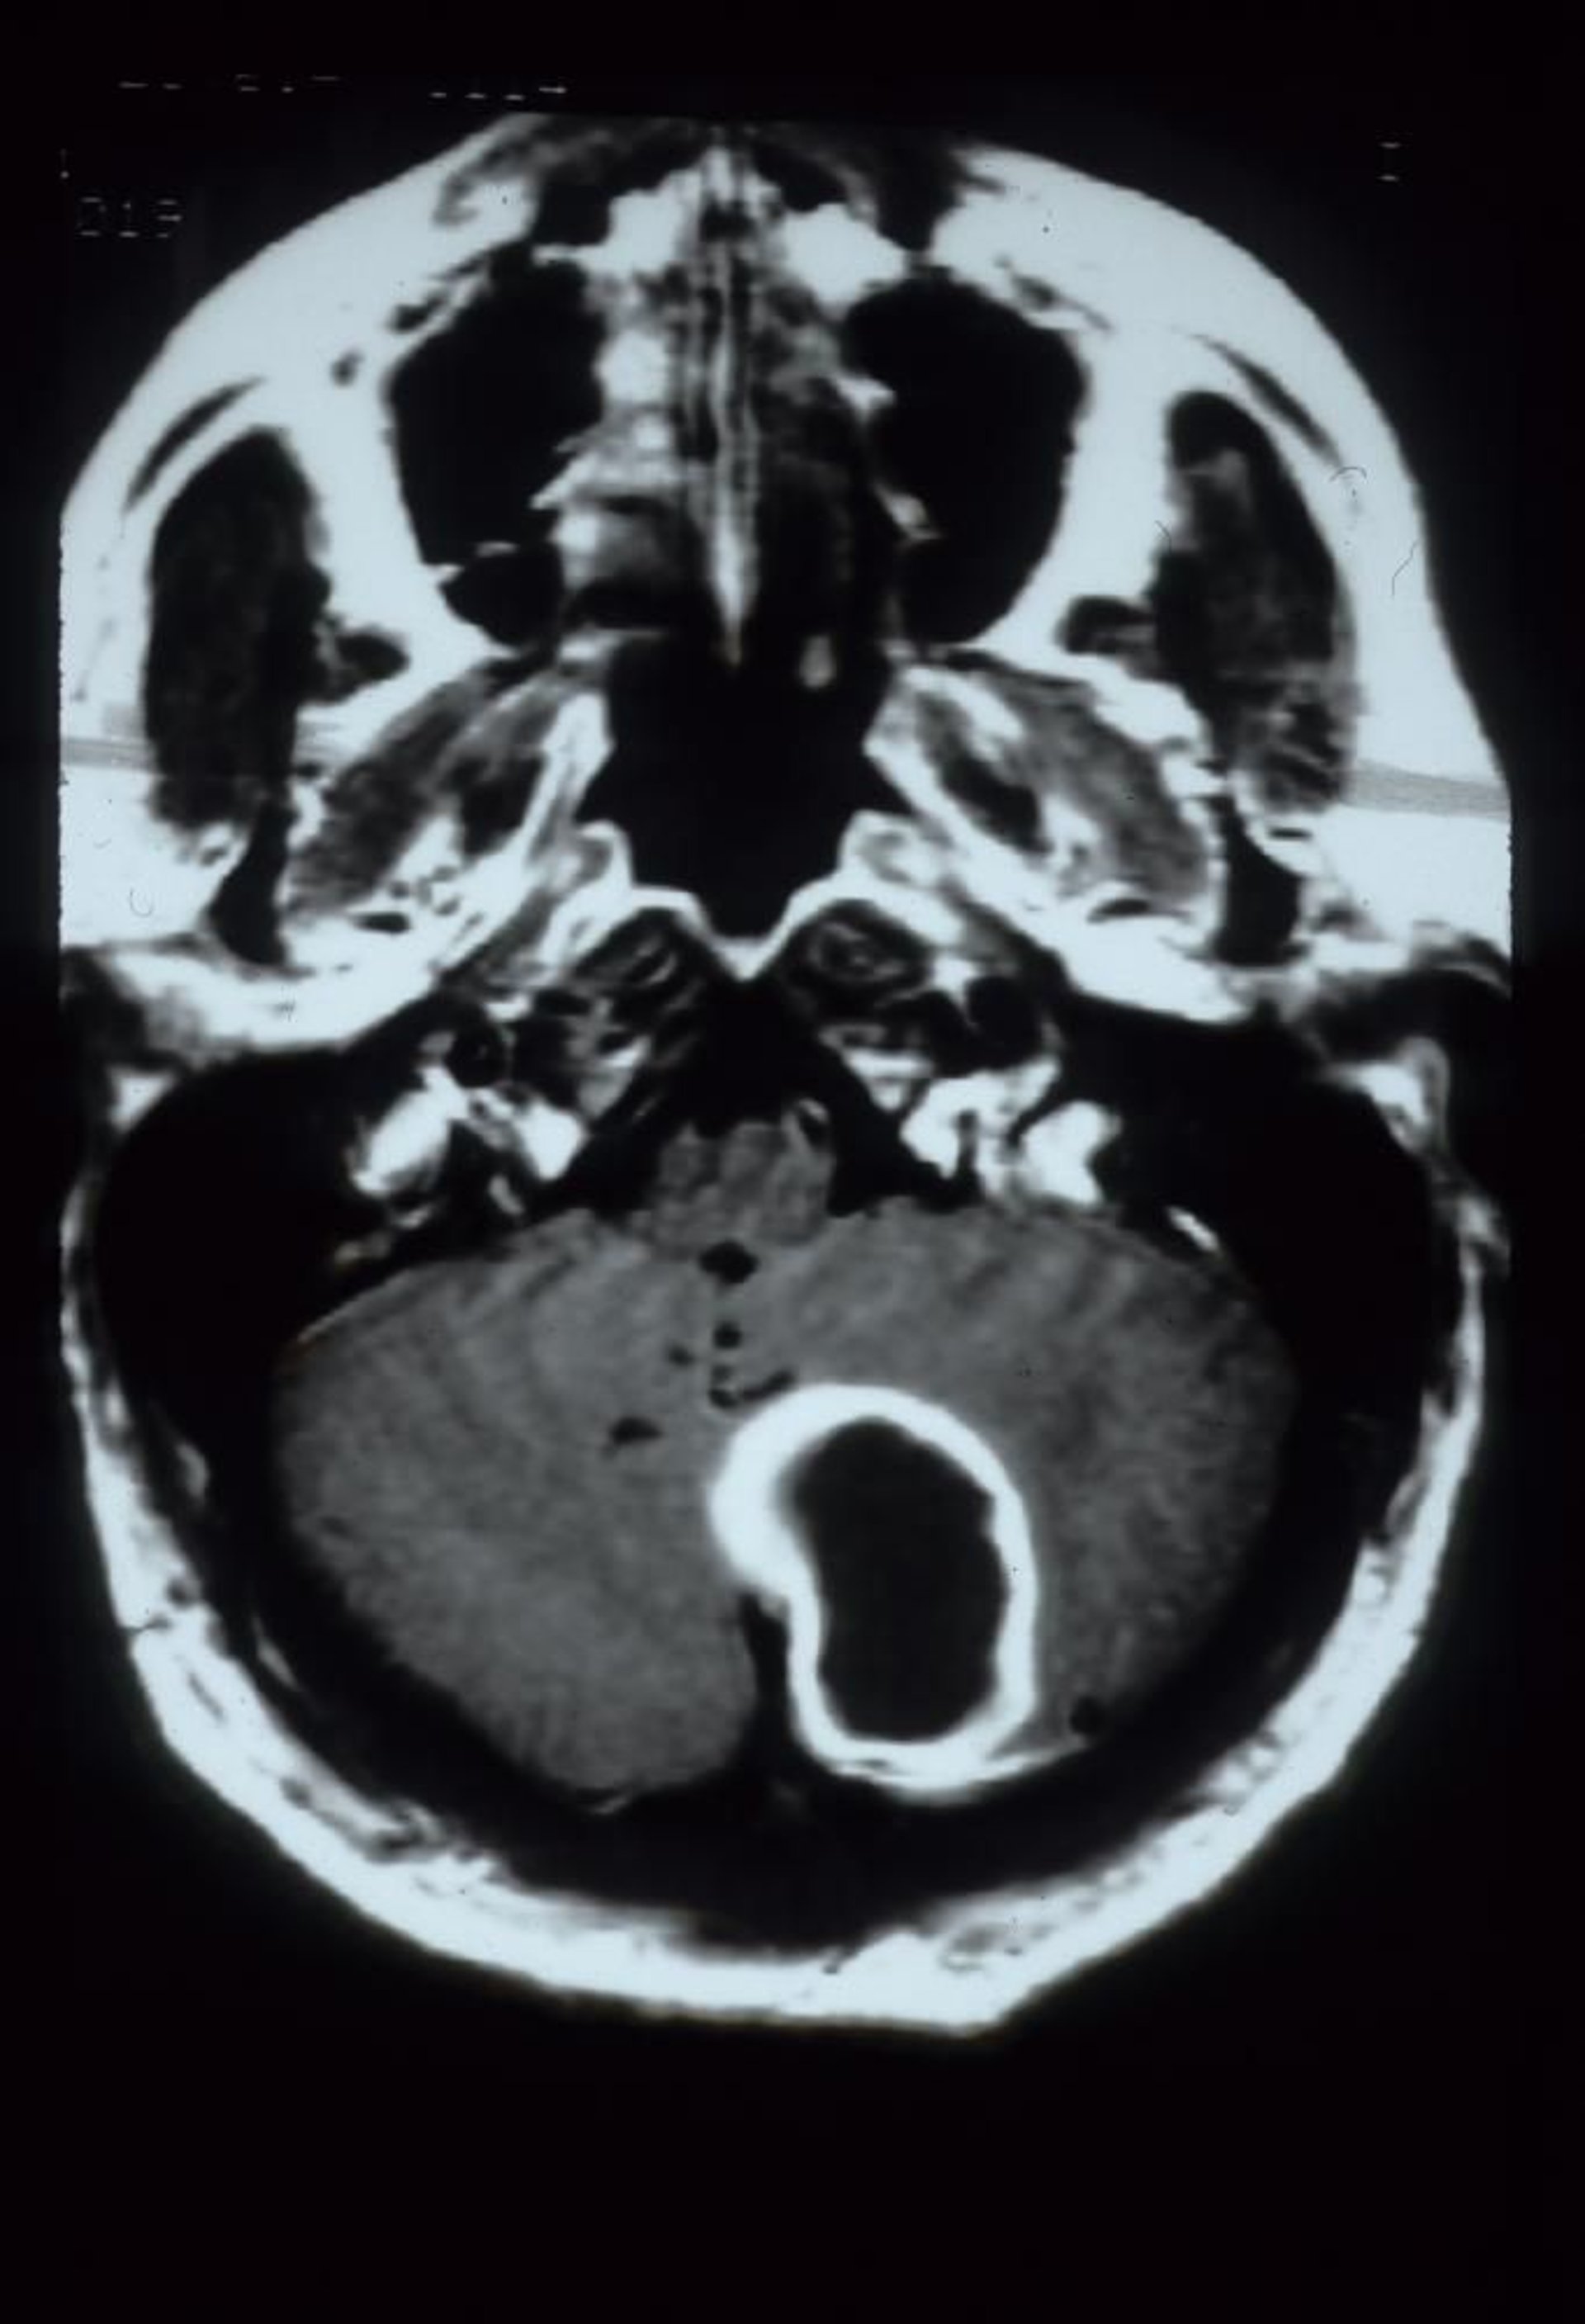

Cerebellar Abscess

This gadolinium-enhanced MRI scan shows a cerebellar abscess, which appears as a large, rim-enhancing cavitary lesion in the left cerebellar hemisphere.

Courtesy of John E. Greenlee, MD.